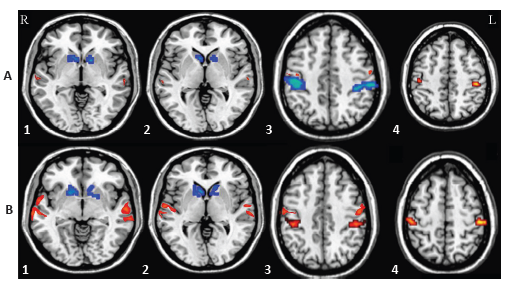

Effect of “three-tong acupuncture” on brain function of patients with spinal cord injury based on magnetic resonance technology

RESULTS AND CONCLUSION: There was a significant improvement in scores of sensory, motor, daily activity and American Spinal Injury Association grading assessment in the two groups after treatment, but there was no significant difference between the two groups (P > 0.05). The amplitude low-frequency fluctuation of bilateral main sensorimotor cortexes of patients in both groups after treatment were significantly increased compared with those before treatment, and the amplitude low-frequency fluctuation of bilateral caudate nucleus after treatment was significantly lower than that before treatment, and there was no significant difference between the two groups after treatment. The regional homogeneity of bilateral anterior and posterior central gyrus and middle temporal gyrus/inferior temporal gyrus between two groups after treatment were significantly higher than those before treatment. The regional homogeneity of bilateral thalamus and caudate nucleus after treatment was significantly lower than that before treatment. There were however no significant difference in the regional homogeneity of these above-mentioned brain areas. The fractional anisotropy of the posterior limb of the internal capsule and the corona radiate after treatment was significantly higher than that before treatment, and the mean diffusivity was decreased compared with that before treatment. There were significant differences in the two groups before and after treatment except for the right radial crown. These findings indicate that “three-tong acupuncture” can improve the remodeling of brain function in patients with spinal cord injury, which may be one of the mechanisms of acupuncture treating spinal cord injury.